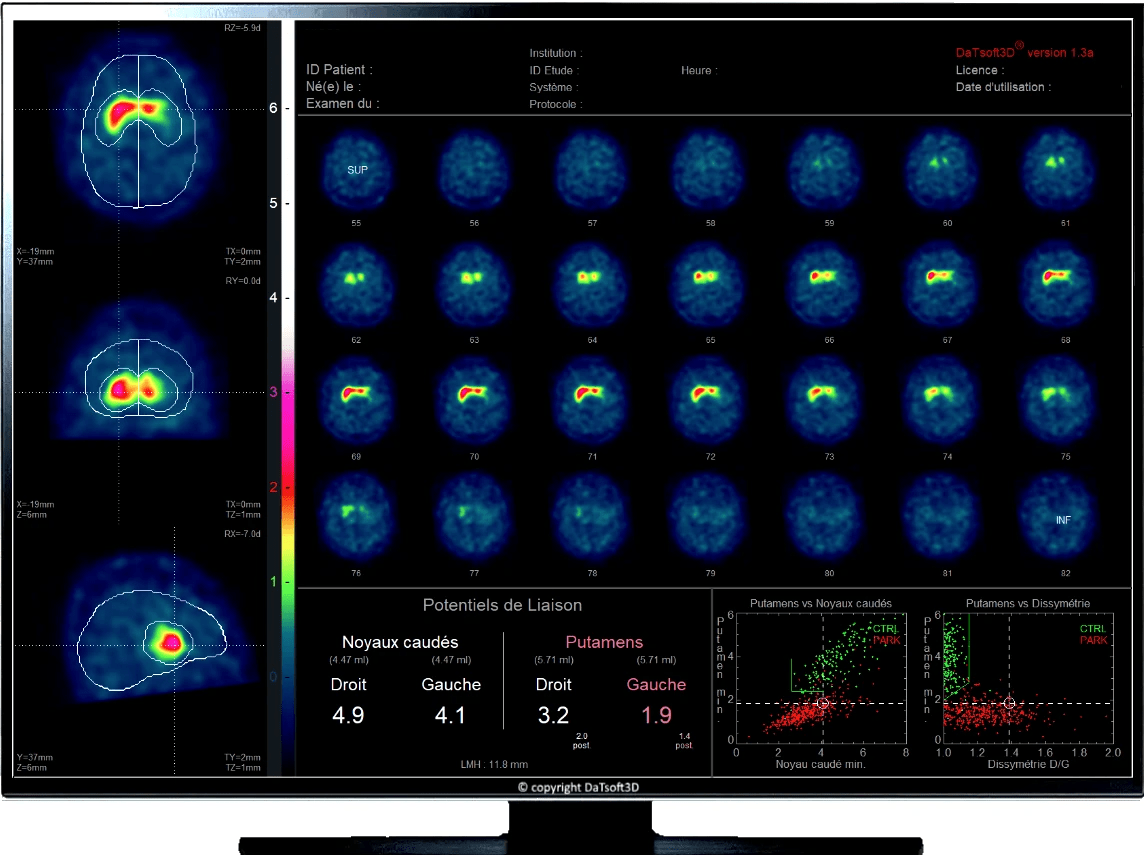

From www.datsoft3d.com

DaTscan quantification software How Long Does It Take To Get Datscan Results This allows the radioactive tracer to circulate in the brain, bind to dopamine transporters, and be interpreted. However, datscan provides more detailed pictures of dopamine brain cells. My symptoms have not been completely alleviated with my current exercise, diet, and prescription medication regimen. How long does a datscan procedure take? Both take images of the brain. The radioactive exposure, and. How Long Does It Take To Get Datscan Results.